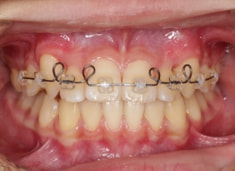

治療開始時